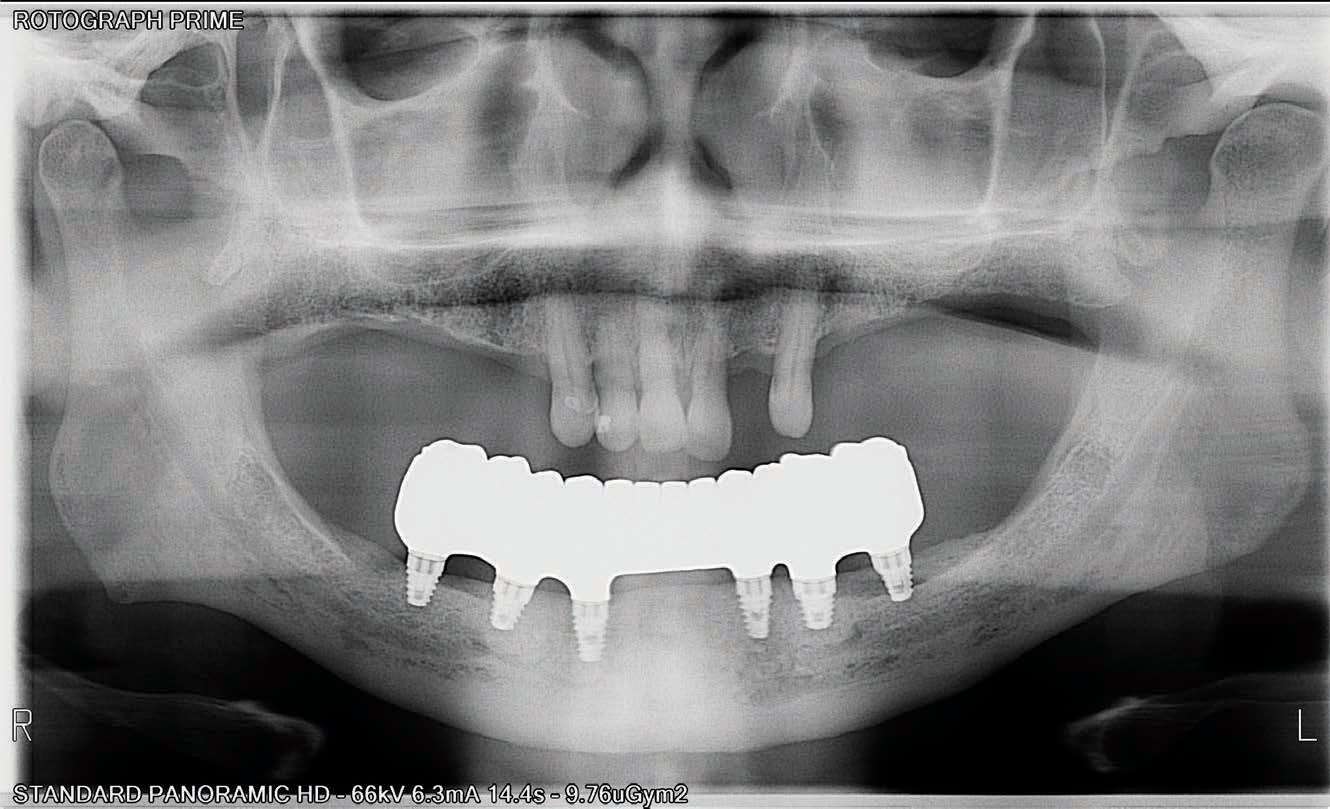

The BioHorizons implants were placed with a good A-P spread, and the bone in the anterior mandible was left in case it was needed at the uncovery appointment (Figure 8). At the uncovery visit, the LightScalpel laser was used to perform a trephine of the posterior implants by placing the surgical guide, marking the osteotomy sites with a Dr. Thompson’s marking stick, and (using a super-pulsed 2W setting) to gently remove the cuff of tissue over the implants (Figure 9). In the anterior mandible, a full-thickness flap was done, and the remaining bone was removed with the PIEZOSURGERY device (Figure 10). The peri-mucosal healing abutments were placed, and a soft-tissue conditioner was placed in the lower denture (Figure 11). After one month of healing, the patient was ready for impressions (Figure 12).

The completed BruxZir Full-Arch Implant Prosthesis is the culmination of great communication with the dental lab team. The final prosthetic result ensured that the patient would not only enjoy his new bridge but would also be able to clean and maintain it with one hand (Figure 20). The relaxed smile view and postoperative Panorex (Figures 21 and 22) shows appropriate lip and tooth display and was a vast improvement over his removable lower denture. The full-face, postoperative photo (Figure 23) of the pleased patient demonstrates that the dictates of aesthetic rehabilitation were met.